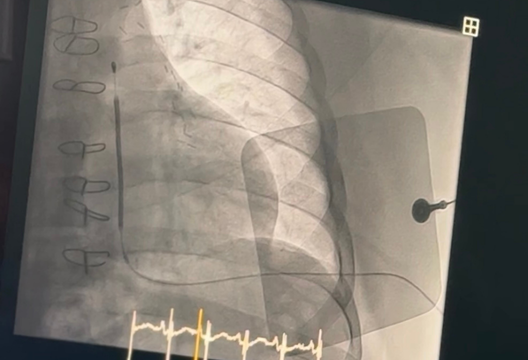

Также, в рамках мастер-класса эксперт из Италии представил технологию имплантации подкожного ИКД EMBLEM™ S-ICD System, которая обеспечивает более безопасную альтернативу. Данное устройство не требует введения электрода в сердце, а помещается под кожу над грудиной. Сам генератор импульсов помещается на левой стороне грудной клетки, рядом с ребрами. Таким образом, система EMBLEM не затрагивает сердце и кровеносные сосуды. Это делает устройство подходящим для пациентов разных возрастов, снижая риски серьезных осложнений и при необходимости делая извлечение более простым и быстрым.

«Важно отметить, что во время имплантации новой системы была использована методика регионарной анестезии Serratus, которая позволяет уменьшить дискомфорт для пациента во время процедуры, а также исключить применение общей анестезии, тем самым ускоряя восстановление пациентов после процедуры», – отметил Омирбек Нуралинов, заведующий интервенционной аритмологии Центра Сердца UMC.